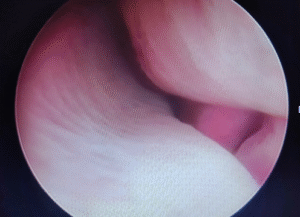

Rinoscopia

Rinoscopia

La rinoscopia veterinaria è una procedura diagnostica che permette di esaminare direttamente l’interno delle fosse nasali, dei seni paranasali e, in alcuni casi, della laringe, utilizzando una sonda endoscopica. Permette anche di identificare e asportare corpi estranei.